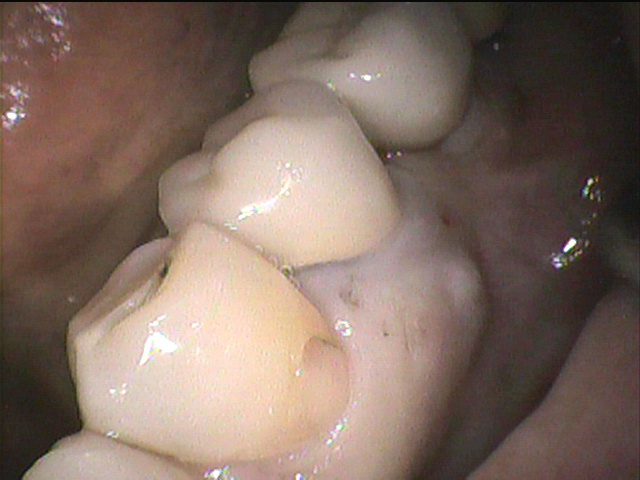

治療前写真

- 奥歯が腫れて、噛むと痛いと言うことで来院されました。

- 抜歯してみると、歯根中央部で真横に折れていました。